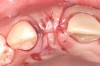

Fig 3. Osteotomy drilled into the ridge, occlusal view.

Figure 3

Fig 4. Implant inserted into the ridge, buccal view. There was a large labial concavity. The implant is seen on the buccal and terminates within the alveolar bone.

Figure 4